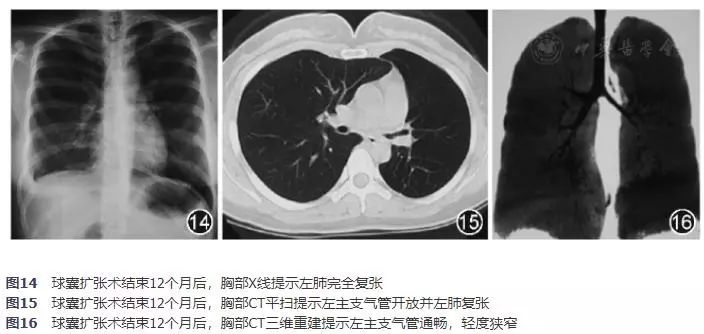

治疗结束12个月对所有患者进行随访,复查支气管镜及气道三维重建,评估治愈率为39.80%(39/98),有效率为32.65%(32/98),无效率为22.45%(27/98),总有效率为72.45%(71/98),治疗结束3个月至12个月期间,2例"治愈"患者及4例"有效"患者发生不同程度气道回缩再狭窄。所有治疗"无效"的患者中,11例闭塞气道经冷冻治疗未打通者,5例接受外科手术治疗,6例放弃外科或其他介入治疗。16例闭塞气道打通,但球囊扩张治疗后仍肺不张或治疗后气道回缩再狭窄,随访时"无效"患者中,4例反复回缩再狭窄患者选择硅酮支架置入术,2例支架取出后气道稳定开放,2例支架取出后即出现气道回缩狭窄后放弃介入及外科手术治疗;另12例患者选择定期复查支气管镜检查,5例气道再次闭塞而放弃治疗,3例因反复出现分泌物堵塞致肺部感染、肺不张而选择外科手术治疗,4例定期复查支气管镜检查狭窄气道无明显变化,后续未予处理。典型病例图示:球囊扩张术结束12个月后复查,胸部X线示左肺不张患者术后左肺完全复张(图14),胸部CT平扫及气道三维重建示左主支气管闭塞患者术后左主支气管重新开放,管腔通畅(图15,图16)。

图14 球囊扩张术结束12个月后,胸部X线提示左肺完全复张

图15 球囊扩张术结束12个月后,胸部CT平扫提示左主支气管开放并左肺复张

图16 球囊扩张术结束12个月后,胸部CT三维重建提示左主支气管通畅,轻度狭窄